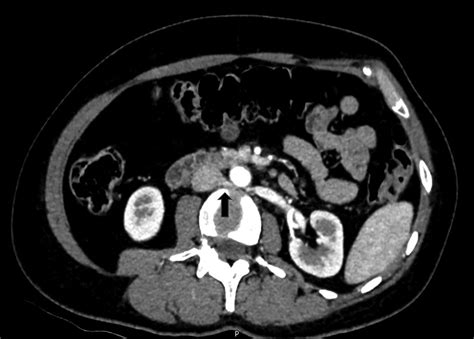

Understanding vascular anomalies can be complex, and one condition that often goes misdiagnosed due to its vague and varied symptoms is Nutcracker Syndrome. If you have been searching for answers regarding persistent pelvic pain, flank discomfort, or hematuria, you might be asking yourself, "What is Nutcracker Syndrome?" At its core, this is a rare venous compression disorder that occurs when the left renal vein is squeezed between two major arteries: the abdominal aorta and the superior mesenteric artery. This compression creates a "nutcracker" effect, impeding the normal flow of blood from the left kidney back toward the heart, leading to a variety of debilitating symptoms.

To grasp the mechanical nature of this condition, it is helpful to visualize the anatomy of the abdomen. The left renal vein travels horizontally across the abdomen to deliver blood from the left kidney into the inferior vena cava. In patients with Nutcracker Syndrome, the angle at which the superior mesenteric artery branches off the aorta is unusually narrow. This anatomical narrowing acts like a clamp, compressing the renal vein.

CT Angiography (CTA) Provides 3D images to measure the precise angle of the artery and the vein diameter.